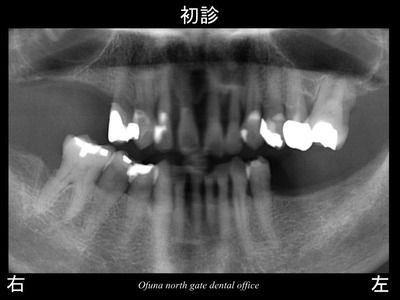

以下は初診時です。

下顎の左右の奥歯 と 下顎前歯部が欠損しており、

歯肉は大きく腫れ、出血があり、グラグラしている歯も非常に多い状態でした。

歯周病検査 の結果、重度歯周病でした。

骨吸収 も大きく起こっていました。